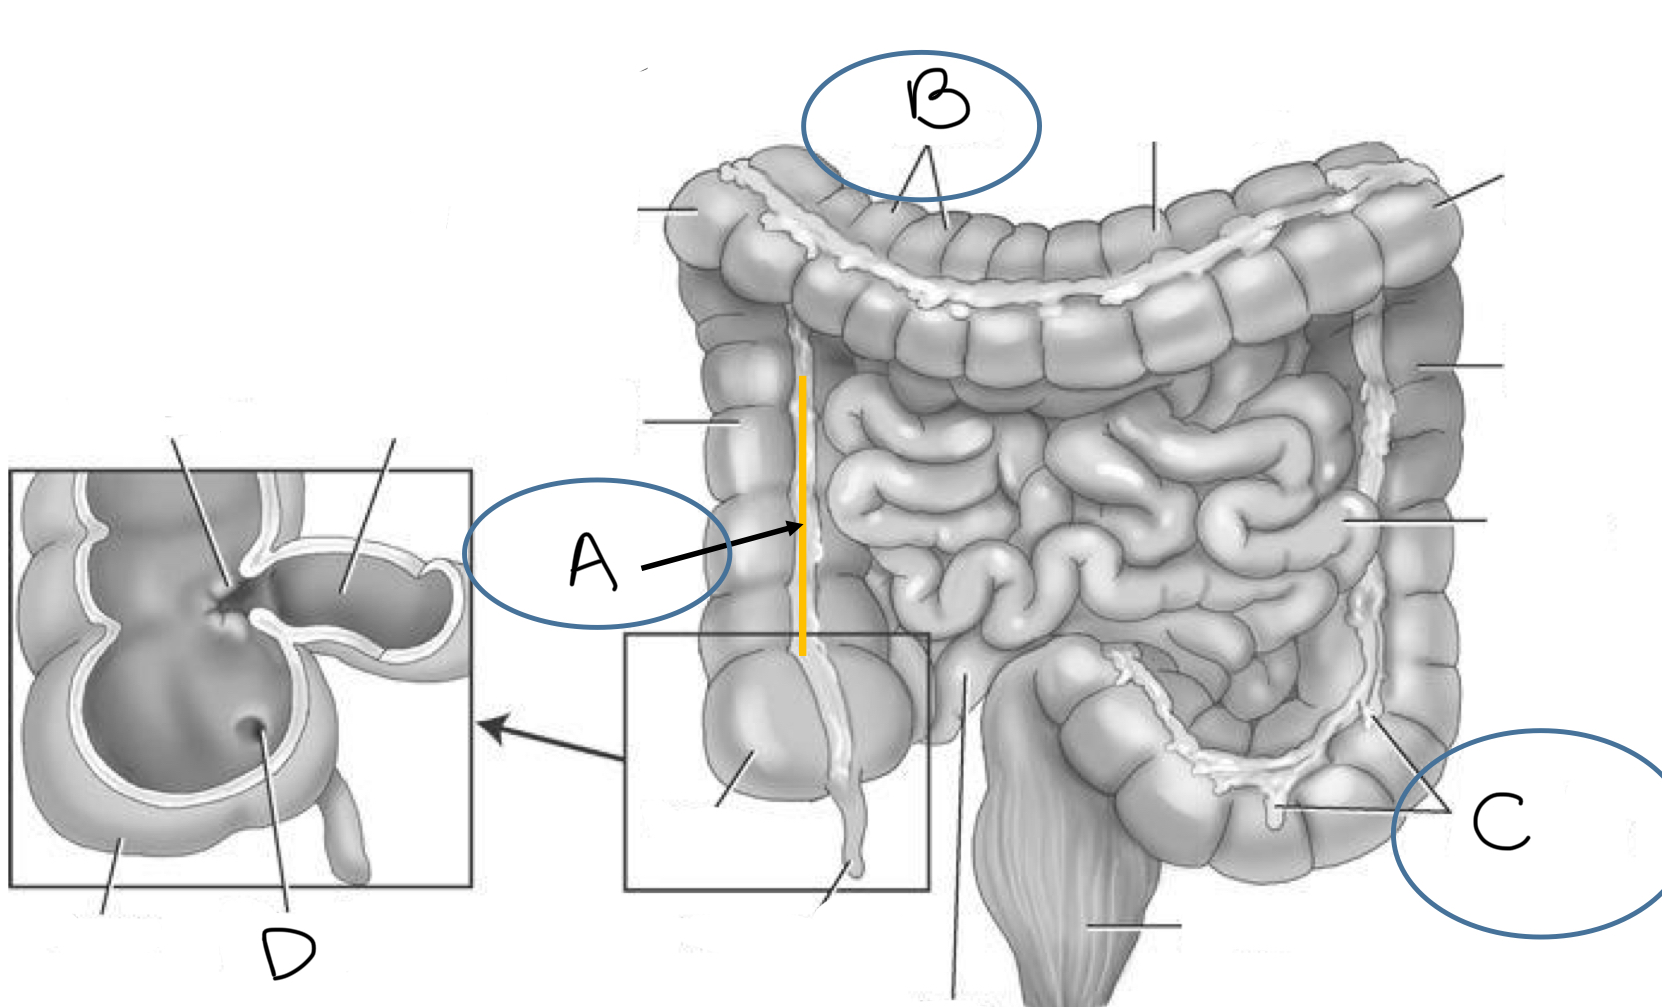

What is A

taeniae coli

What is B

haustra

What is C

epiploic appendages

What is D

orifice of appendix

What is the pink area?

terminal ileum